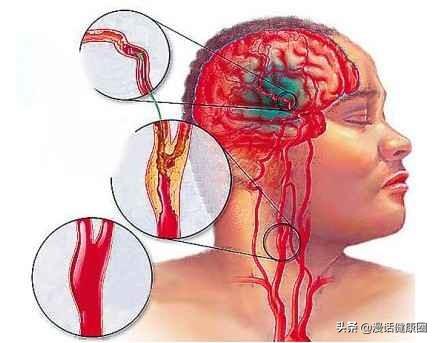

Pour connaître les signes d'une attaque cérébrale, il faut d'abord savoir comment elle se produit.

Notre cerveau gère presque toutes les fonctions de notre corps et est connu comme le commandant du corps. Le cerveau dépend du sang pour transporter l'oxygène et les nutriments dont il a besoin. Lorsque les vaisseaux sanguins sont bloqués pour diverses raisons, le cerveau est incapable d'obtenir de l'oxygène et des nutriments et meurt, entraînant la perte de fonctions de notre corps, ce qui est appelé infarctus cérébral. Les fonctions des différentes parties du cerveau étant différentes, les patients auront des séquelles plus ou moins importantes selon la localisation et l'étendue de la nécrose. Certaines personnes peuvent n'avoir qu'un léger vertige et découvrir qu'elles ont subi un infarctus cérébral lorsqu'elles se rendent à l'hôpital pour un examen (la plupart des patients atteints d'infarctus cérébral lacunaire sont découverts au cours de l'examen). Certains patients garderont des séquelles telles que l'hémiplégie, l'immobilité, la cécité, le retard mental, voire la mort.

L'un des signaux les plus importants avant la survenue d'un infarctus cérébral est l'AIT, qui se traduit en chinois par "attaque ischémique transitoire". Cela signifie que les vaisseaux sanguins du cerveau se contractent et se spasment soudainement, entraînant une diminution de l'apport d'oxygène et de nutriments au cerveau, ce qui provoque des symptômes similaires à ceux d'un infarctus cérébral. Cependant, le vaisseau sanguin n'est pas bloqué à ce moment-là, il est seulement spasmé et rétréci, et après quelques minutes ou quelques heures, il reviendra de lui-même à la normale (le temps ne dépasse généralement pas une heure), et les symptômes disparaîtront. La survenue d'un AIT indique que les vaisseaux sanguins cérébraux de la personne ont des problèmes et que le risque d'infarctus cérébral à l'avenir est très élevé. À ce moment-là, le patient doit se rendre d'urgence à l'hôpital pour un examen et des mesures de prévention.

L'infarctus cérébral est en fait un trouble de l'irrigation sanguine des vaisseaux sanguins du cerveau, qui se traduit par une irrigation sanguine insuffisante du cerveau, ce qui déclenche l'ischémie et l'hypoxie et aggrave encore la nécrose ischémique ou le ramollissement du tissu cérébral. L'infarctus cérébral représente la majorité des accidents vasculaires cérébraux dans la pratique clinique, et les types d'accidents vasculaires cérébraux les plus courants sont les suivantsThrombose cérébrale, infarctus lacunaire et embolie cérébraleetc.

L'infarctus cérébral est divisé en plusieurs types en fonction des différentes causes de l'infarctus : la rupture de la plaque causée par l'athérosclérose, formant un thrombus qui bloque les vaisseaux sanguins cérébraux, forme un infarctus cérébral ; l'embolie formée dans la région du cœur en raison d'une fibrillation auriculaire, d'un flutter auriculaire, d'une insuffisance cardiaque, d'une maladie valvulaire cardiaque, etc., qui pénètre dans les vaisseaux sanguins cérébraux avec le flux sanguin pour bloquer les vaisseaux sanguins cérébraux, forme également un infarctus cérébral ; l'occlusion des petits vaisseaux sanguins des artères cérébrales en raison d'un durcissement et de lésions, etc. forme également un infarctus cérébral, et ces infarctus cérébraux se produisent lentement en termes de pathogenèse. Ces infarctus cérébraux, bien qu'ils soient lents à se produire, mais lorsque les vaisseaux sanguins cérébraux sont soudainement bloqués, en particulier les vaisseaux sanguins importants responsables de l'approvisionnement en sang du cerveau, l'infarctus cérébral se produit d'un seul coup et il n'y a pas trop de précurseurs pour que nous puissions y faire face. L'infarctus cérébral se produit directement lorsqu'il entraîne directement dans le corps une hémiplégie, une aphasie, une ataxie, qui peuvent être accompagnées de maux de tête sévères, de nausées, de vomissements et d'autres symptômes, et l'état peut rapidement évoluer vers un infarctus cérébral. Par conséquent, pour prévenir l'infarctus cérébral, nous devrions toujours contrôler activement le risque à partir de la pathogenèse, et l'idée de se fier aux précurseurs ou aux symptômes précoces pour juger du risque d'infarctus cérébral est très difficile à mettre en œuvre pour prévenir le risque et intervenir à l'avance.

L'infarctus cérébral est également appeléInfarctus cérébral ou accident vasculaire cérébral ischémique (AVC ischémique cérébral)Ce terme désigne la nécrose ou le ramollissement du tissu cérébral dû à un manque d'apport sanguin au cerveau, qui se produit à la suite d'une ischémie ou d'une hypoxie.